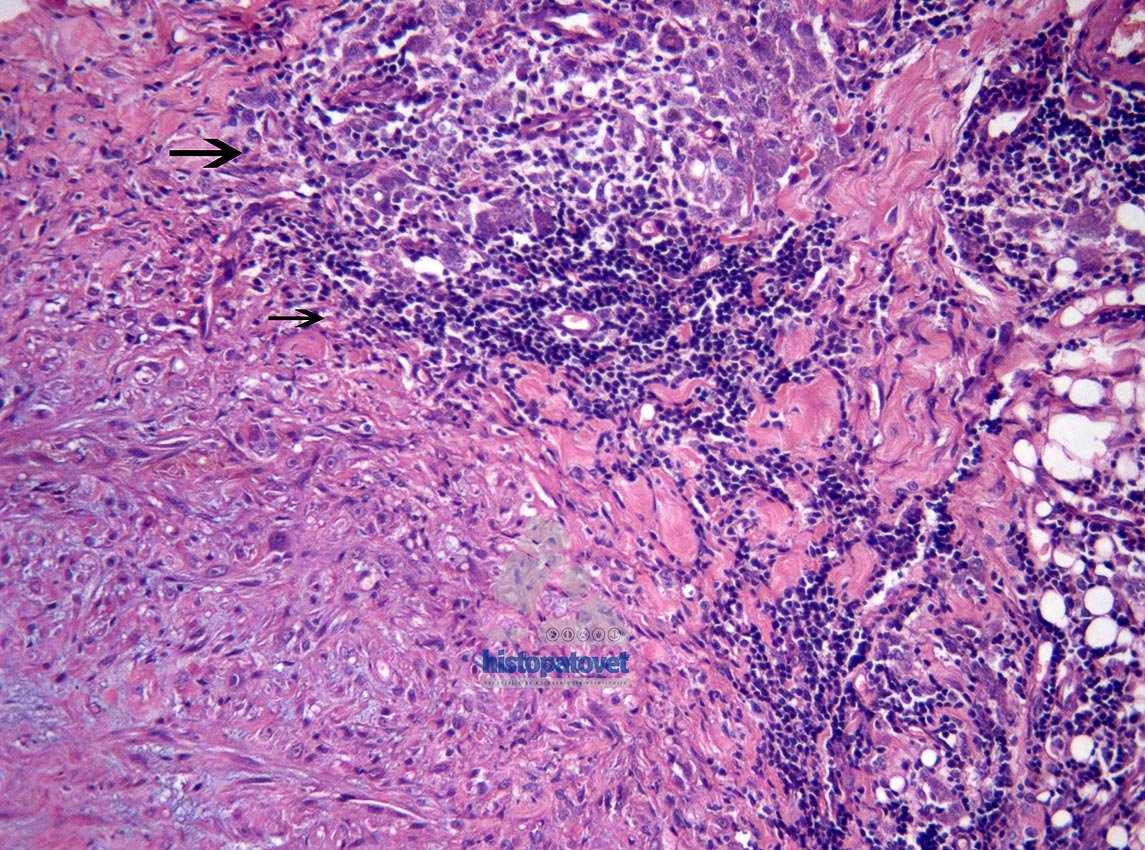

El principal hallazgo histopatológico es encontrar especialmente en la periferia del tumor una respuesta inflamatoria sobre todo a base de linfocitos y macrófagos. Estos últimos fagocitando algún material extraño, que generalmente son remanentes de la vacuna o aluminio (coadyuvante). Ver las siguientes tres figuras(3,4,5).

Fig.3. La masa principal en el centro. En la periferia( ver flechas), Hay acúmulos de células inflamatorias.

Fig. 5. Macrófagos, fagocitando un material granular(flecha grande) y linfocitos( flecha pequeña).En el plan diagnostico, antes de decidir el tipo de biopsia a utilizar, es recomendable tomar una radiografía de tórax( por lo menos dos vistas laterales), para descartar alguna metástasis.